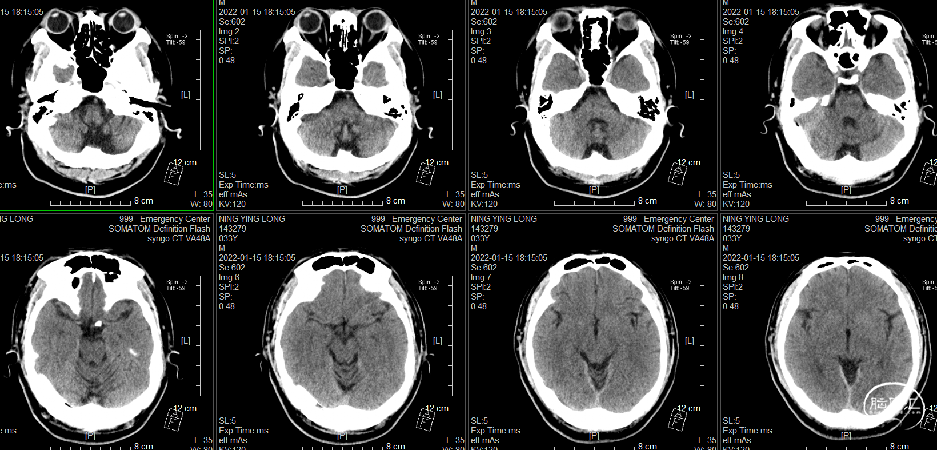

●头颅CT(2022-1-4,外院):上矢状窦、右侧横窦密度增高,可疑静脉窦血栓,建议MR平扫+MRV成像检查。

头颅CT(2022-1-4)

头颅CT(2022-1-10)